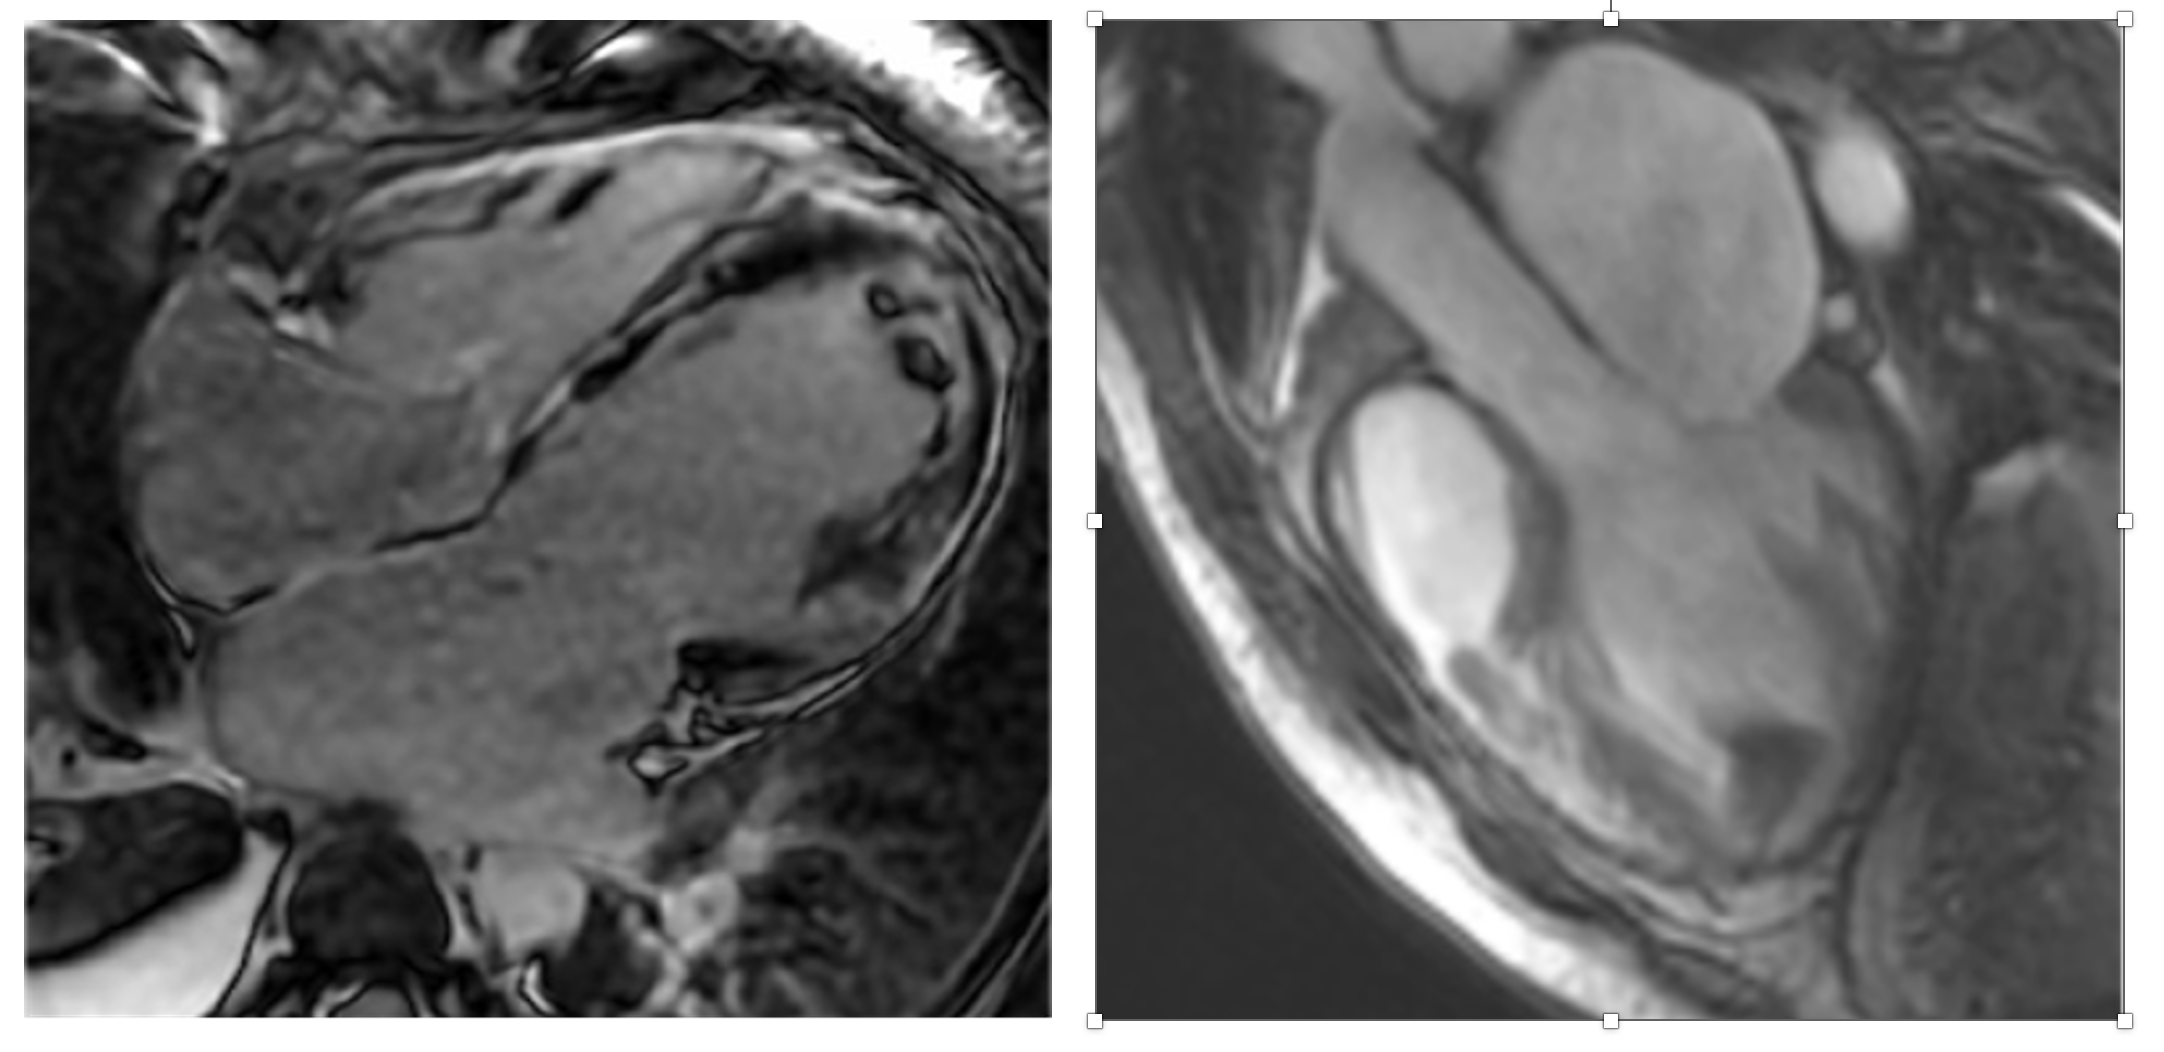

Second CMR: 4 Chamber view with LGE and 3 Chamber view showing both LV and RV thrombi